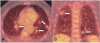

Amyloidosis comprises a rare spectrum of protein deposition diseases that diffusely or focally affect any organ. Amyloid's variable clinical presentation and nonspecific disease course often cause it to evade early diagnosis. This pictorial essay aims to familiarize radiologists with the pathophysiology of amyloidosis, to describe the basic classifications of amyloidosis, and to use multimodality imaging to illustrate its varied appearance throughout the body. This review highlights the diagnostic challenge of interpreting radiographic studies in patients with hematologic malignancies and concurrent amyloidosis. Radiologists should consider amyloid in chronically ill patients or patients with hematologic malignancies who have unusual/unexpected imaging findings.